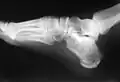

Calcâneo esquerdo. Superfície lateral.